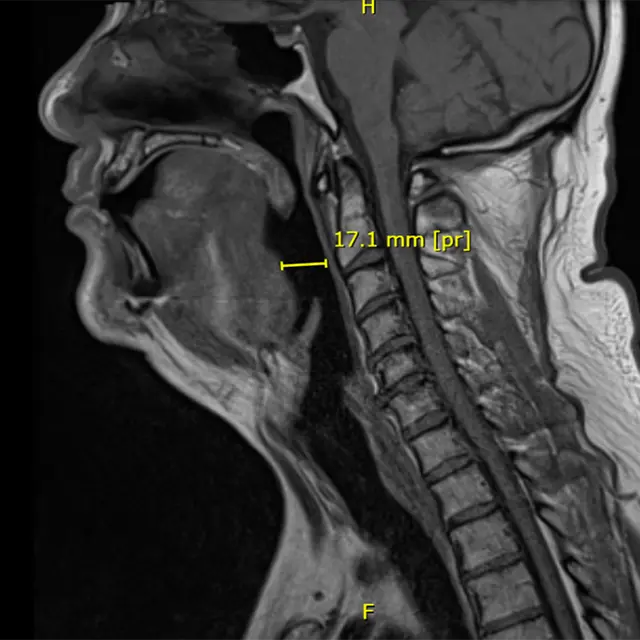

Post-operation MRI of airway with BTTT OSA implant in-situ

Post-operation MRI of airway with BTTT

Device in-situ (Image: Francois Oosthuizen)

Their answer was an innovative implant called the Biological Tendon-like Tether Technology (BTTT). It is a small scaffold that helps the body grow its own tissue to gently hold the airway open during sleep. The scaffold is placed at the base of the tongue, where it helps the body grow strong collagen fibers. These fibers eventually replace the implant and do the job naturally.

In 2024, the South African Health Products Regulatory Authority (SAHPRA) approved the first human trials. Conducted with UCT’s Clinical Research Centre, the early results showed strong promise for treating OSA.